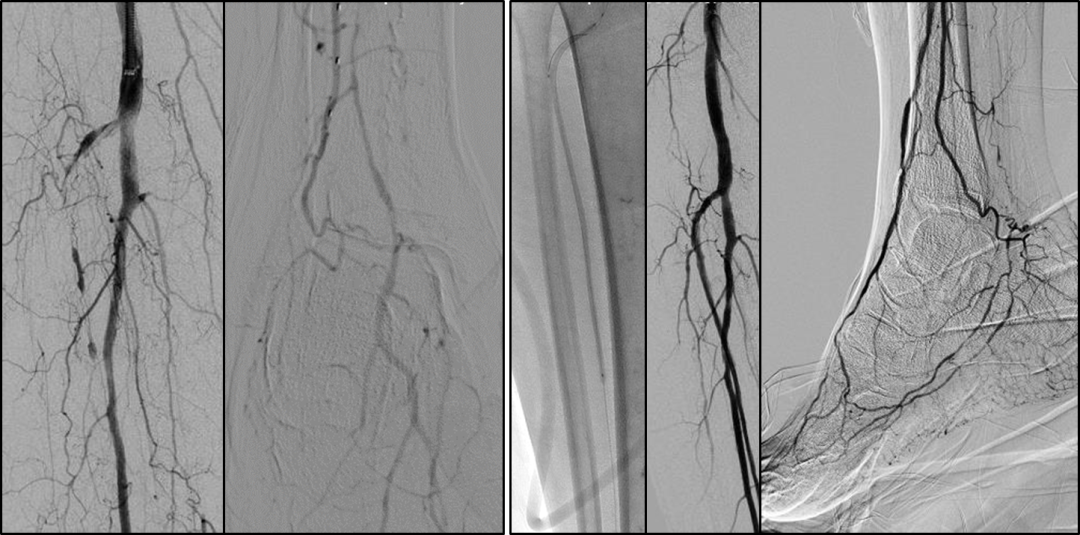

BTK 标准化开通流程

Ante-True Lumen

Fail + short lesion

Fail →Retro puncture

Fail → SAFARI/CART/r-CART

Fail + long lesion

Fail → PA/PTA

Fail → ATA

Fail → PCA

Fail → Puncture

Fail → Pedal arch

Antegrade access with retrograde wireguided

通过深入剖析解剖规律、明确技术选择边界、并提出一套简化的标准化流程,为临床医生处理BTK-CTO病变提供了清晰、实用的操作指南,有助于提高手术成功率,改善CLTI患者的保肢预后。